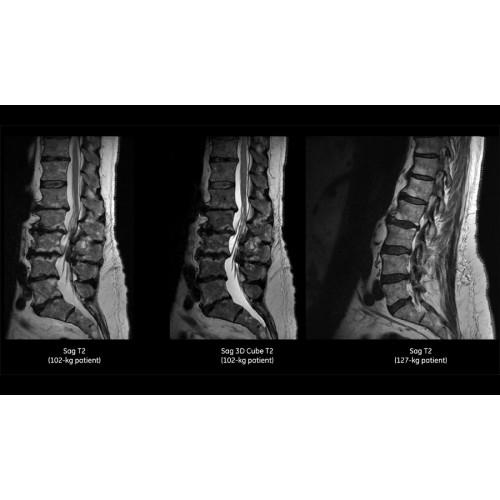

• Технология Digital Surround Technology (DST) — это новая технология объемной оцифровки данных, объединяющая сигналы от каждого элемента катушки. Прекрасное соотношение сигнал/шум и чувствительность поверхностных катушек в сочетании с превосходной однородностью и высокой проникающей способностью встроенной радиочастотной катушки — все это позволяет создавать качественные изображения не только позвоночника, но и всего тела.

Благодаря революционному программному пакету Silent Suite уровень шума снижается до 77 дБ, что всего на 3 дБ выше уровня окружающей среды. Программный пакет Silent Suite теперь включает полный пакет приложений для исследования ЦНС (T1, T2 FLAIR, DWI10, МРА). Кроме того, мы расширили возможности визуализации Silent за пределы ЦНС для исследований скелетно-мышечной системы и позвоночника. Silent Suite – платформа, содержащая в себе все импульсные последовательности для бесшумного сканирования.

Технологии SIGNA Pioneer позволяют проводить полное исследование брюшной полости при свободном дыхании, минимизируя артефакты движения пациента, в том числе с МР-динамическим контрастированием.